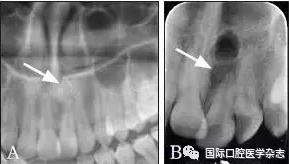

阻生牙拔除后,拔牙窩骨質(zhì)愈合前的X線片顯示為不同程度的透射影(圖9)。因此,了解患者的拔牙史也是有必要的。

A:拔牙前全景片的局部影像;B:阻生牙拔除1周后。

圖 9 尚未愈合的拔牙窩

Fig 9 Unhealing wound of thetooth extraction socket